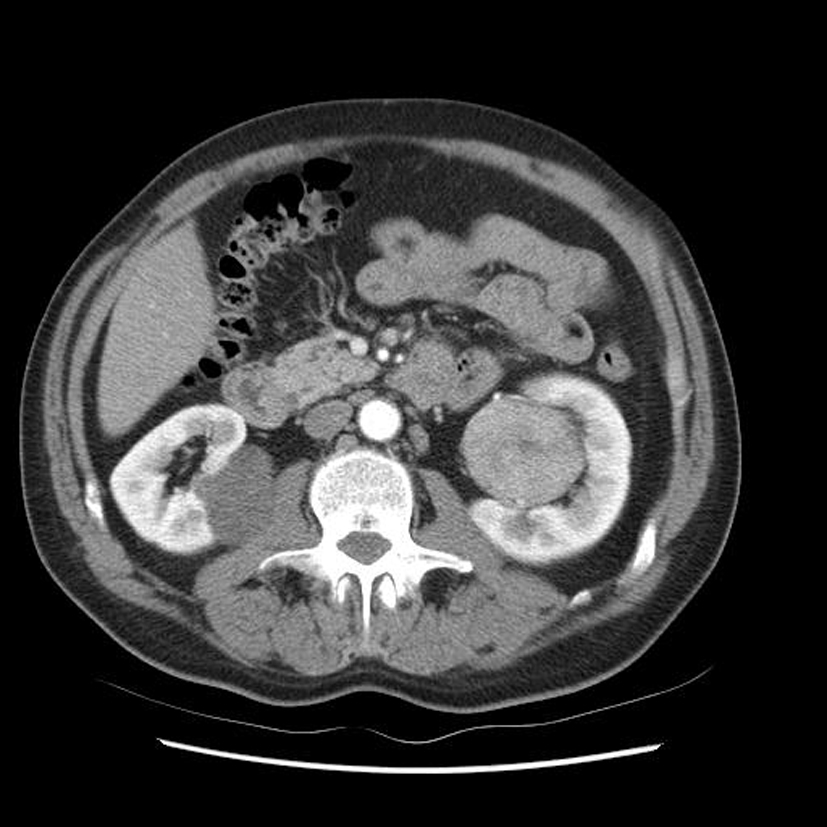

Diagnostic?

Tumeur rénale droite avec adénopathies au niveau du pédicule rénal